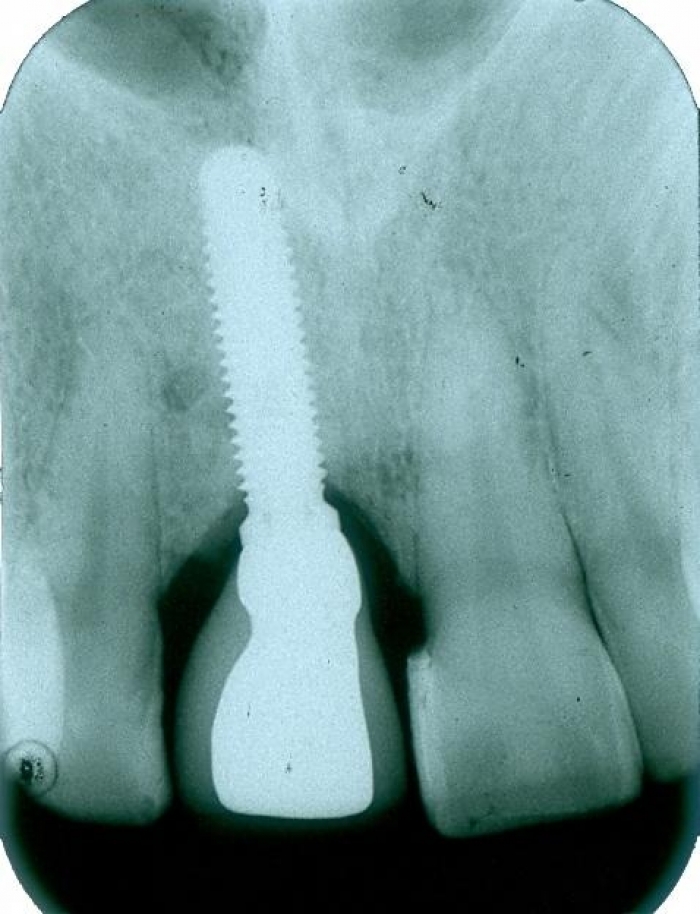

Raio X com prótese de porcelana sobre o implante